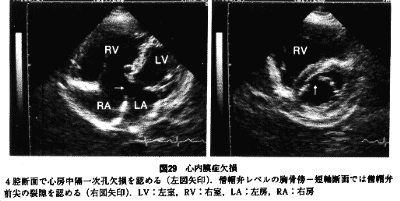

• 心内膜炎について知っておくべきこと

心内膜炎、または感染性心内膜炎は、心臓の部屋と弁の内層のまれな感染症です。緊急の治療が必要な重篤な状態ですが、抗生物質で治療可能です。

心内膜炎は、心臓の部屋と弁を覆う組織層である心内膜に影響を与えます。心内膜炎に罹患している場合、心内膜が炎症を起こす可能性があります。

さらに、医師は、経胸壁または経食道心エコー図などの心エコー図を要求する場合があります。心エコー図は音波を使用して人の心臓の画像を作成します。この検査により、医師は心臓の構造を検査し、植生として知られる細菌や細胞の塊がないかどうかを確認できます。